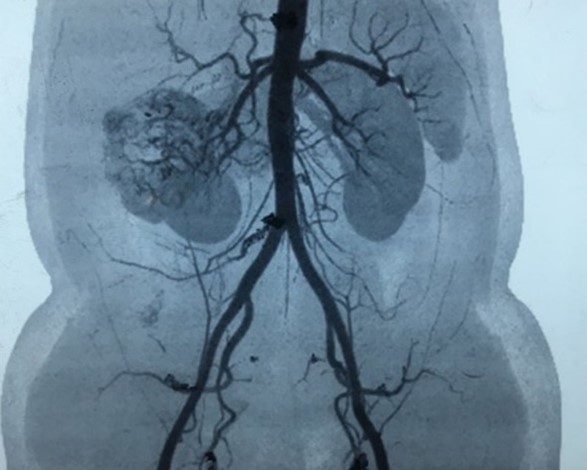

- Renal Angiography – is an imaging test to look at the arteries in your kidneys. This is important prior to surgery. This facilitates the urooncologist surgeon to dissect and trace the arteries and veins of kidney but also educates about the feeding tumour vessels. This can be done by conventional Angiography or CT Renal Angiography.